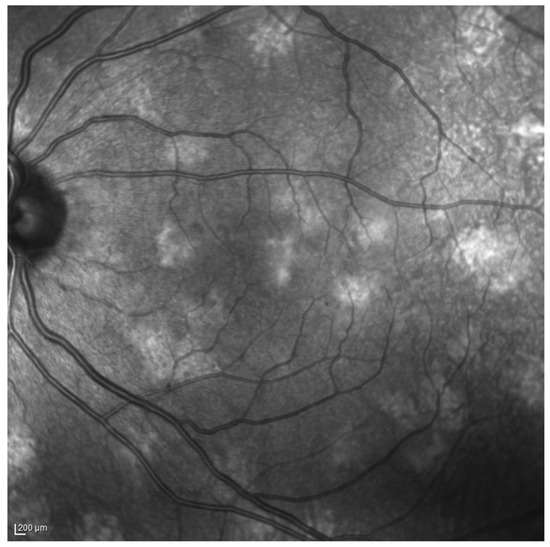

- Moramarco, A.; Mallone, F.; Sacchetti, M.; Lucchino, L.; Miraglia, E.; Roberti, V.; Lambiase, A.; Giustini, S. Hyperpigmented spots at fundus examination: A new ocular sign in Neurofibromatosis Type I. Orphanet J. Rare Dis. 2021, 16, 147. [Google Scholar] [CrossRef]

- Moramarco, A.; Giustini, S.; Nofroni, I.; Mallone, F.; Miraglia, E.; Iacovino, C.; Calvieri, S.; Lambiase, A. Near-infrared imaging: An in vivo, non-invasive diagnostic tool in neurofibromatosis type 1. Graefe’s Arch. Clin. Exp. Ophthalmol. 2018, 256, 307–311. [Google Scholar] [CrossRef]

4. Hyperpigmented Spots (HSs) in NF1